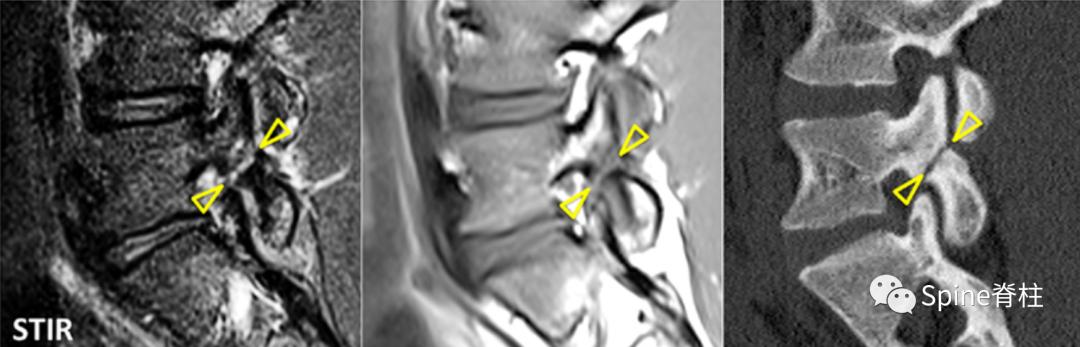

MRI提示的峡部裂(红圈)